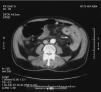

Un hombre de 73 años, con hipertensión y fibrilación auricular bajo tratamiento de warfarina, ingresó con dolor abdominal, distensión y hematemesis de sangre oscura. Presentaba anemia (hemoglobina 8.4g/dL), tiempo de protrombina prolongado y tiempo parcial de tromboplastina con un INR > 15. Se sometió a una endoscopia. No se identificaron lesiones, reportando únicamente sangre en el duodeno. Se introdujo un colonoscopio pediátrico de 150cm de longitud, mostrando mucosa violácea con ulceraciones en el duodeno distal con sangrado espontáneo (fig. 1a). A medida que el endoscopio se avanzó al yeyuno, se observaron úlceras más grandes y profundas (fig. 1b). Aproximadamente, 15cm distal al ángulo de Treitz (fig. 1c), el intestino se encontraba extremadamente edematoso, presentando necrosis isquémica circunferencial. Las ulceraciones se volvían más profundas y aproximadamente a los 25cm distales al ángulo de Treitz (fig. 1d) había una obstrucción luminal completa. La tomografía computarizada mostró una pared engrosada en el duodeno distal y el yeyuno proximal, con edema y hemorragia intramural (fig. 2), sin obstrucción arterial ni venosa. El hematoma espontáneo del intestino delgado es una complicación rara de la terapia anticoagulante. Hasta donde conocemos, este es el primer caso de un hematoma intramural que desencadenó un íleo por anticoagulante, cuyo diagnóstico primario fue realizado durante la endoscopia.